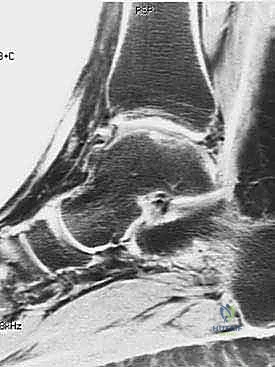

Diagnostic Imaging and Electromyography

Magnetic Resonance Imaging (MRI) is the gold standard imaging modality. T2-weighted sequences are highly sensitive for detecting early denervation edema within the supraspinatus and infraspinatus muscle bellies, which often precedes visible atrophy. MRI is also critical for identifying space-occupying lesions, such as paralabral ganglion cysts, which frequently originate from posterosuperior labral tears.

Electromyography and Nerve Conduction Studies (EMG/NCS) remain the objective standard for confirming neuropathy. Findings of increased latency, decreased amplitude, fibrillations, and positive sharp waves help localize the lesion to either the suprascapular notch (affecting both supraspinatus and infraspinatus) or the spinoglenoid notch (affecting only the infraspinatus).

Clinical & Radiographic Imaging